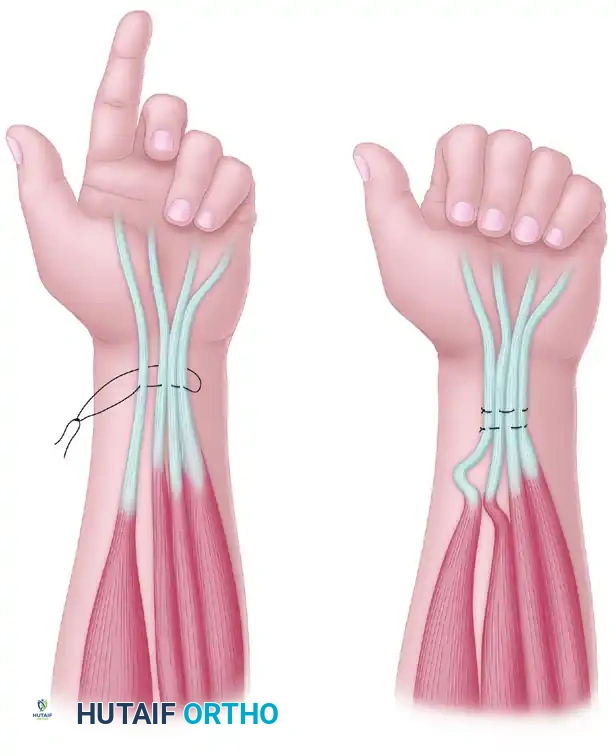

* Oberlin Transfer: Transfer of expendable motor fascicles from the ulnar nerve (usually supplying the FCU) directly to the biceps motor branch of the musculocutaneous nerve.